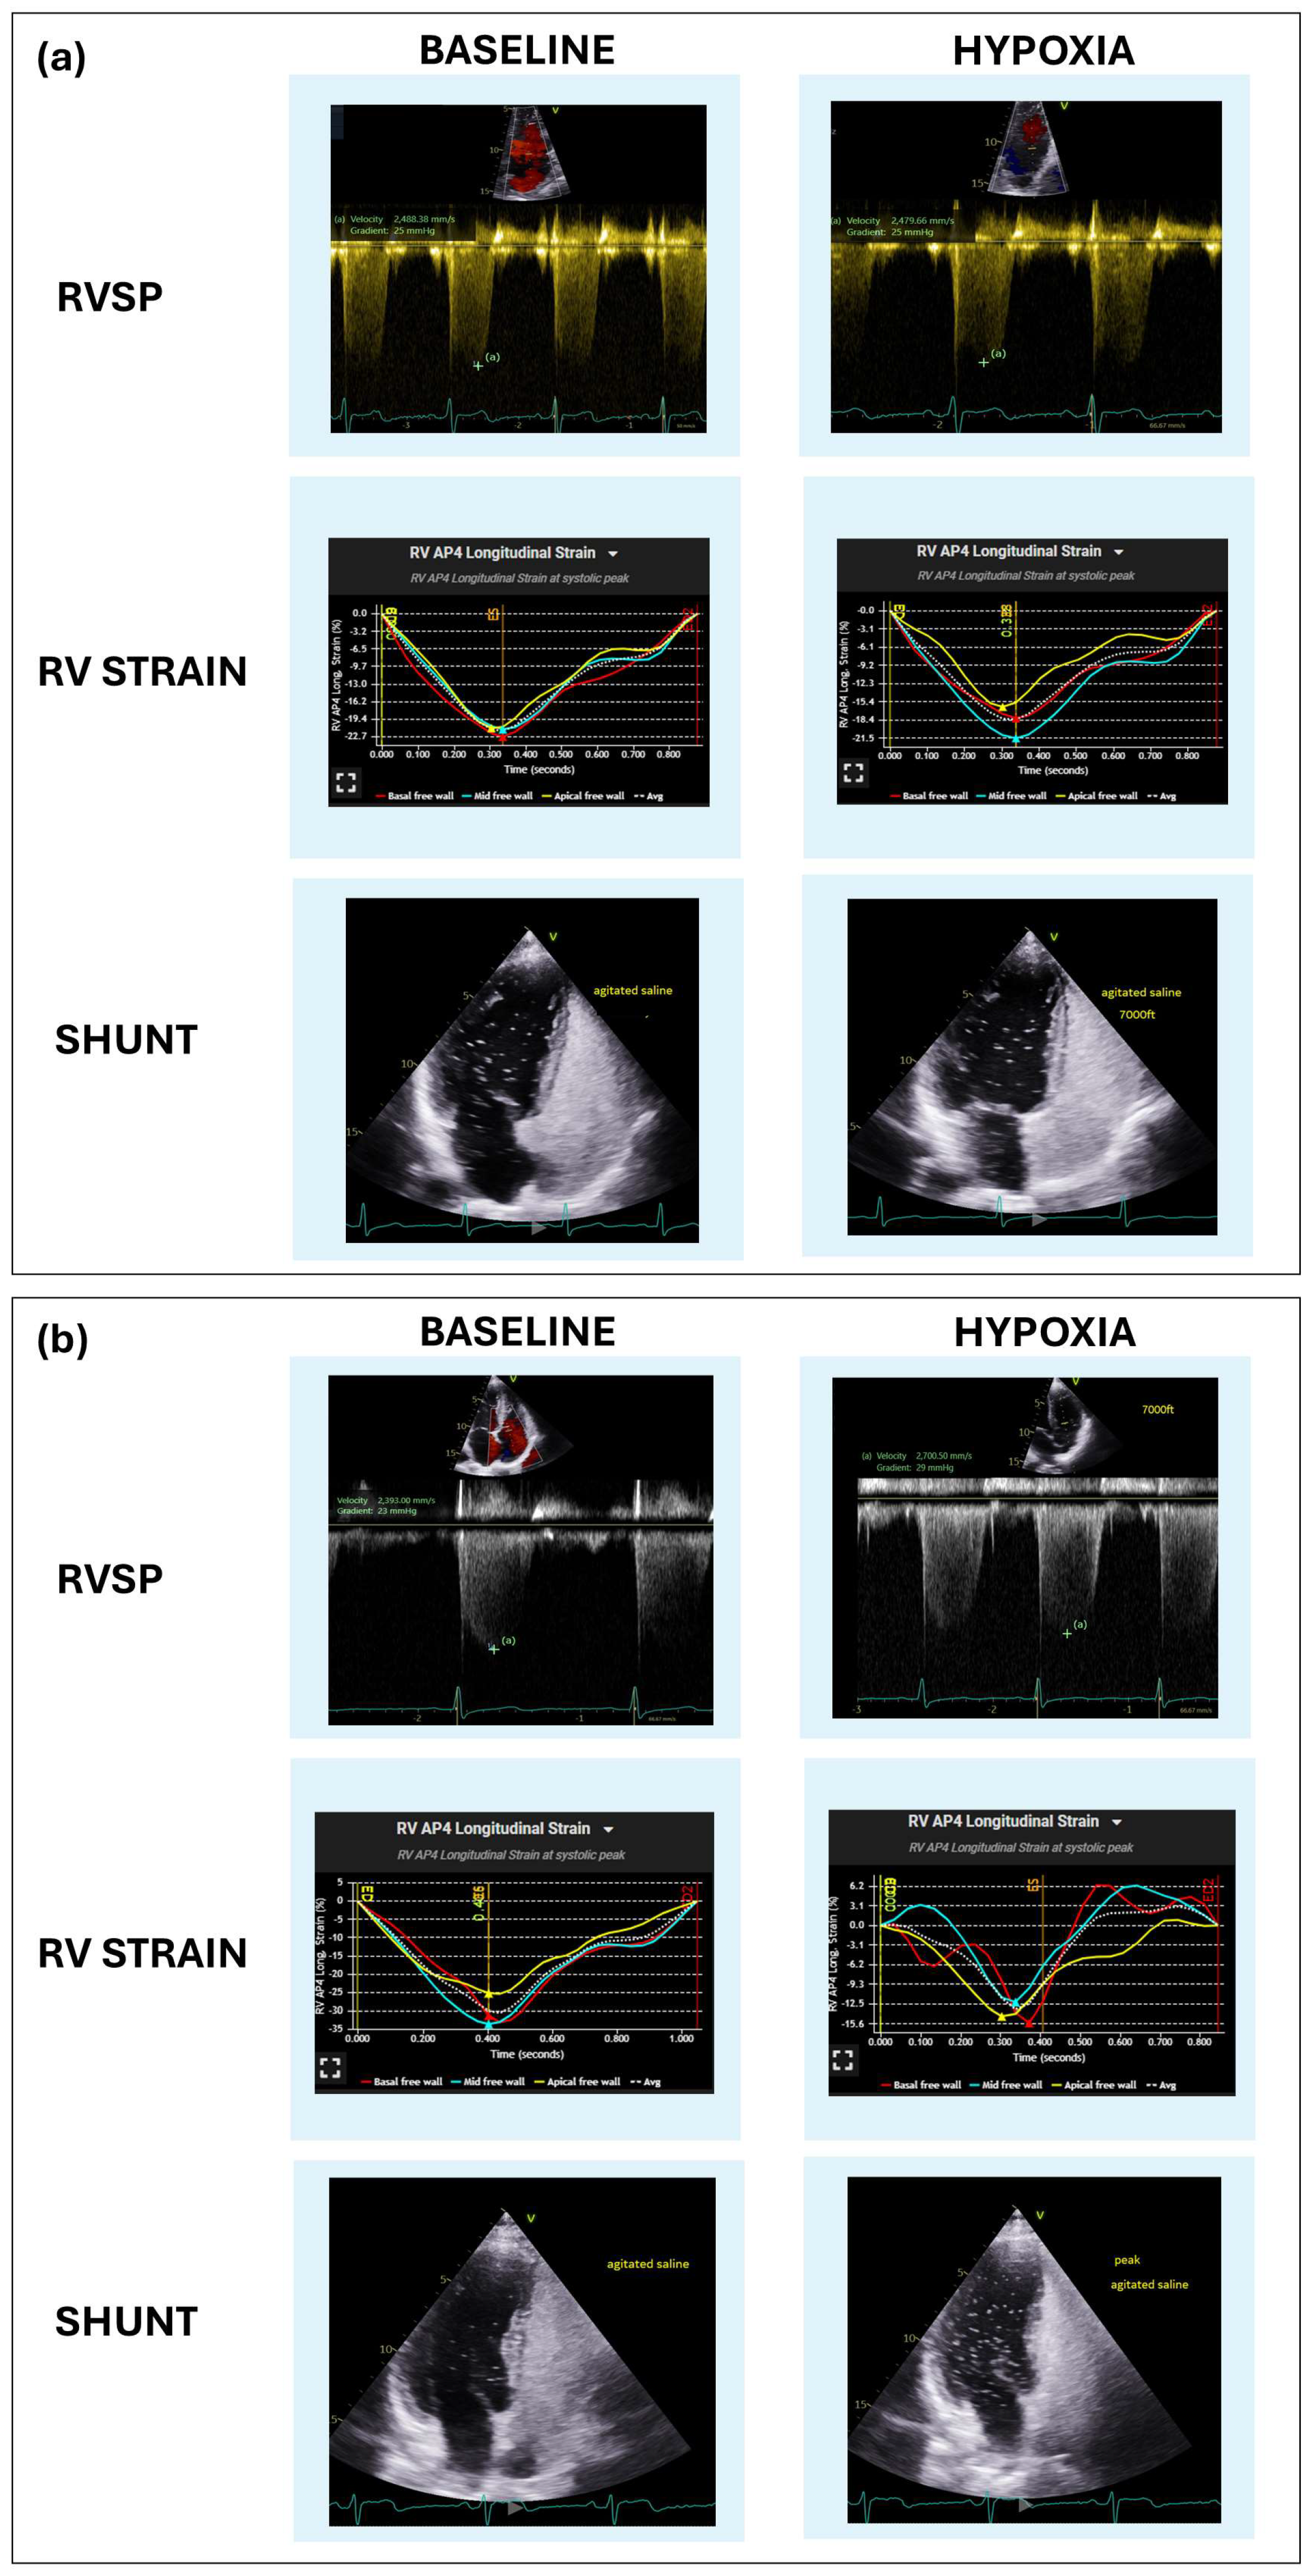

| RVSP (mmHg) | 26 (23–30.5) | 29 (25–36.5) | <0.001 |

| RV strain (%) | −19.6 ± 3.99 | −17.37 ± 4.17 | <0.01 |

| Shunt presence | 57 (45.6%) | 66 (52.8%) | <0.01 |